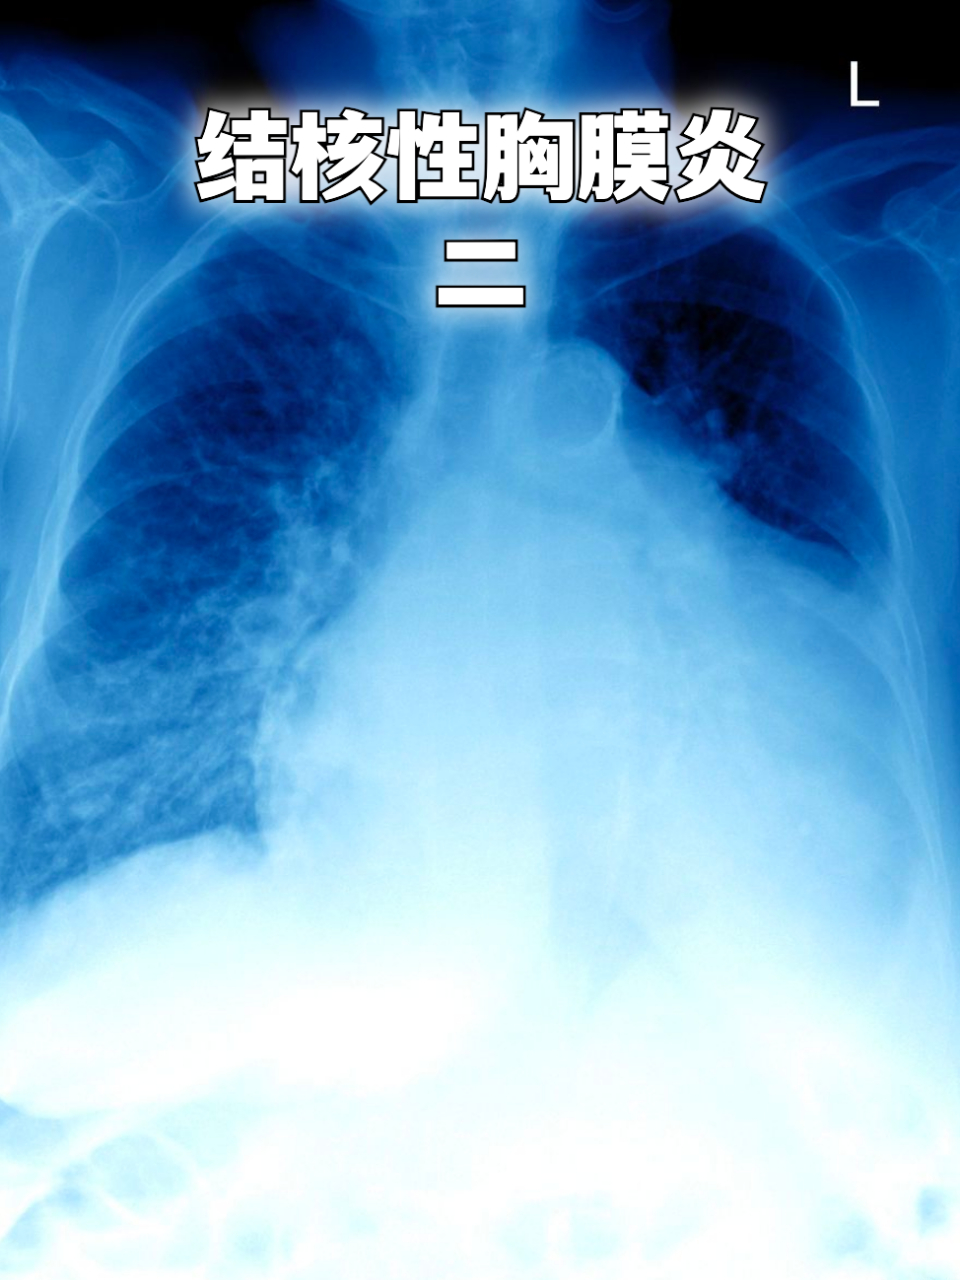

结核性胸膜炎二 #胸膜炎# 我是用的胸腔闭式引流 第一天胸水引流: 医